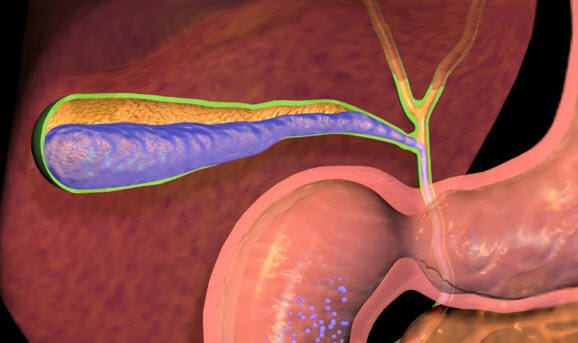

Холелитиаз характеризуется образованием камней и конкрементов в желчном пузыре и холедохе. Процесс протекает без ярких симптомов в течение нескольких лет. Перемещение камня в проток может вызвать застой желчи и колики длительностью в несколько часов. Частые печеночные колики приводят к воспалению в жёлчном пузыре, острому холециститу. Образованные камни в холедохе развивают холангит. В случае нахождения в протоке нескольких камней ставится диагноз холедохолитиаз.

Образование конкрементов может протекать без симптомов долгие годы. Но перемещение камня по протоку часто закрывает просвет канала при сокращении желчного пузыря. Появляется желчная колика с сильной болью, после чего происходит обструкция холедоха.

Непроходимость желчевыводящих путей в течение нескольких часов вызывает острый холецистит, а застой в канале желчи развивается холангит. Если обтурация камня произошла в Фатеровой ампуле, то начинается острый панкреатит.